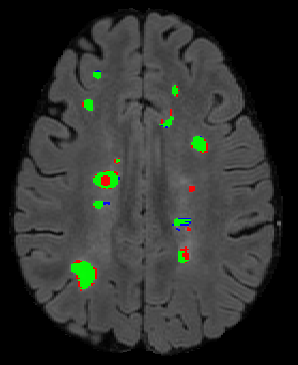

The detection of new multiple sclerosis (MS) lesions is an important marker of the evolution of the disease. The applicability of learning-based methods could automate this task efficiently. However, the lack of annotated longitudinal data with new-appearing lesions is a limiting factor for the training of robust and generalizing models. In this work, we describe a deep-learning-based pipeline addressing the challenging task of detecting and segmenting new MS lesions. First, we propose to use transfer-learning from a model trained on a segmentation task using single time-points. Therefore, we exploit knowledge from an easier task and for which more annotated datasets are available. Second, we propose a data synthesis strategy to generate realistic longitudinal time-points with new lesions using single time-point scans. In this way, we pretrain our detection model on large synthetic annotated datasets. Finally, we use a data-augmentation technique designed to simulate data diversity in MRI. By doing that, we increase the size of the available small annotated longitudinal datasets. Our ablation study showed that each contribution lead to an enhancement of the segmentation accuracy. Using the proposed pipeline, we obtained the best score for the segmentation and the detection of new MS lesions in the MSSEG2 MICCAI challenge.